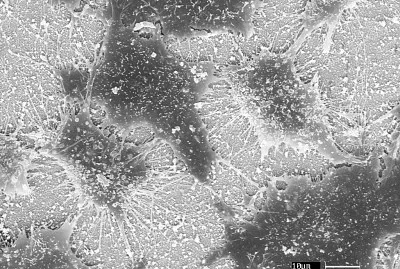

Célula endotelial sob ti...

0.0

10